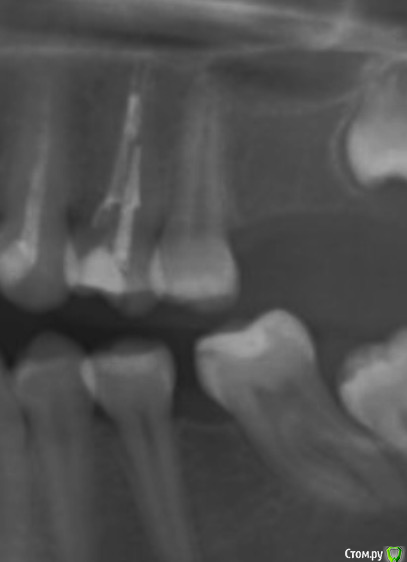

Вот старый снимок, лучше видно как залечен зуб и свежее фото, сохраняется отёк, болит если надавливать.

На снимках кармана не видно, нужен очный осмотр и зондирование десневой борозды, как альтернатива проведение компьютерной томографии.